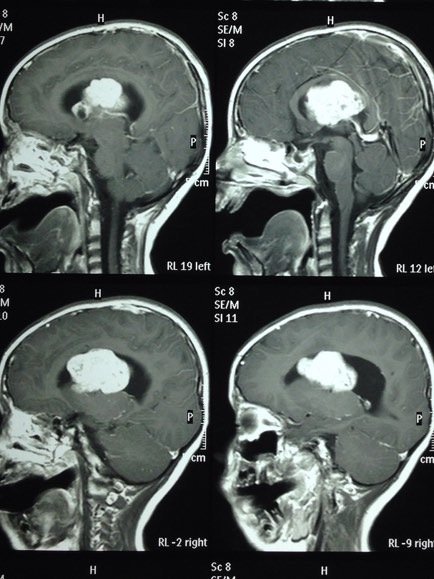

ESCLEROSIS TUBEROSA